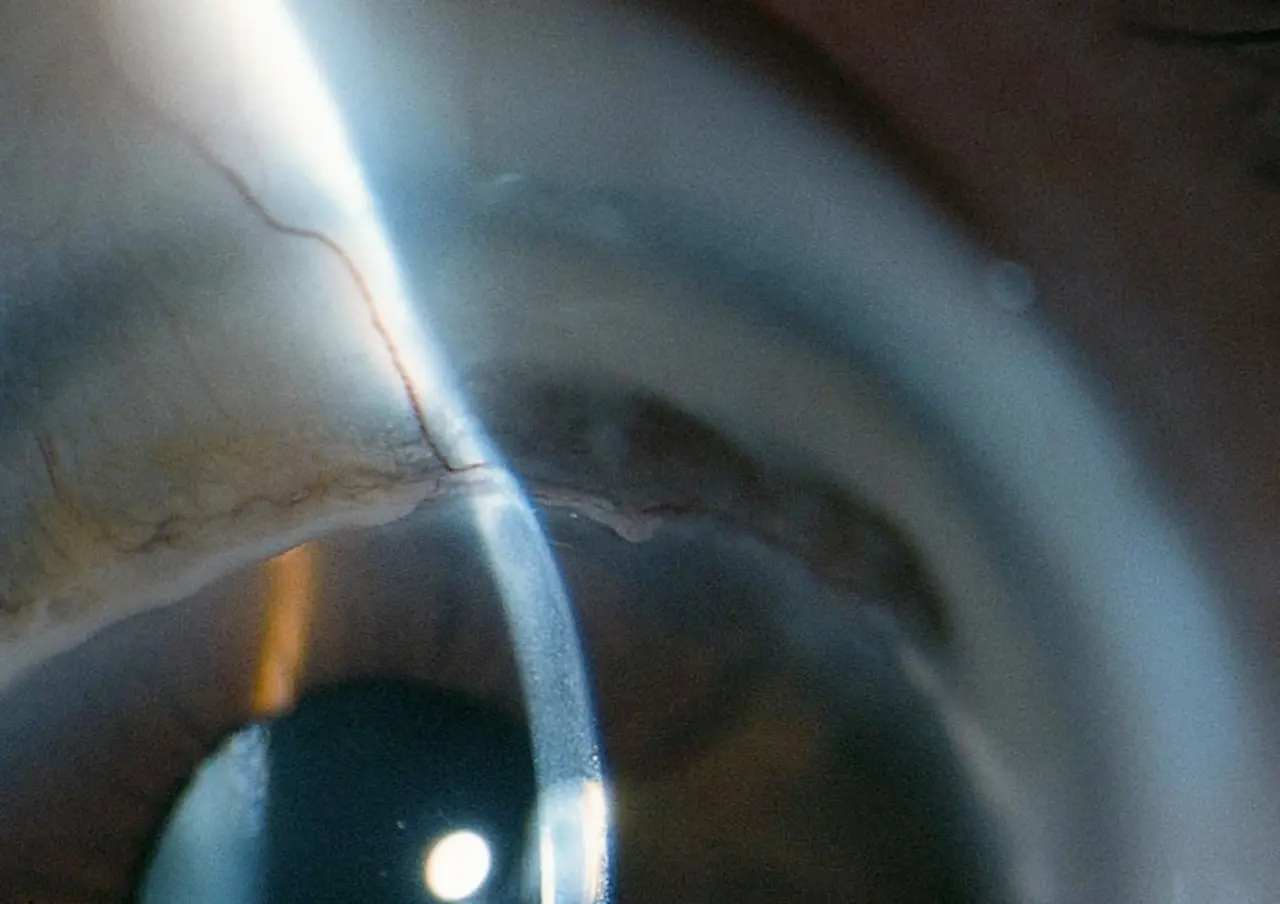

“We only treated two eyes, but it was the first time a Terrien could be stopped and partially reversed,” Farhad Hafezi, MD, PhD, OSN Europe Edition Board Member, said in a telephone interview with Ocular Surgery News